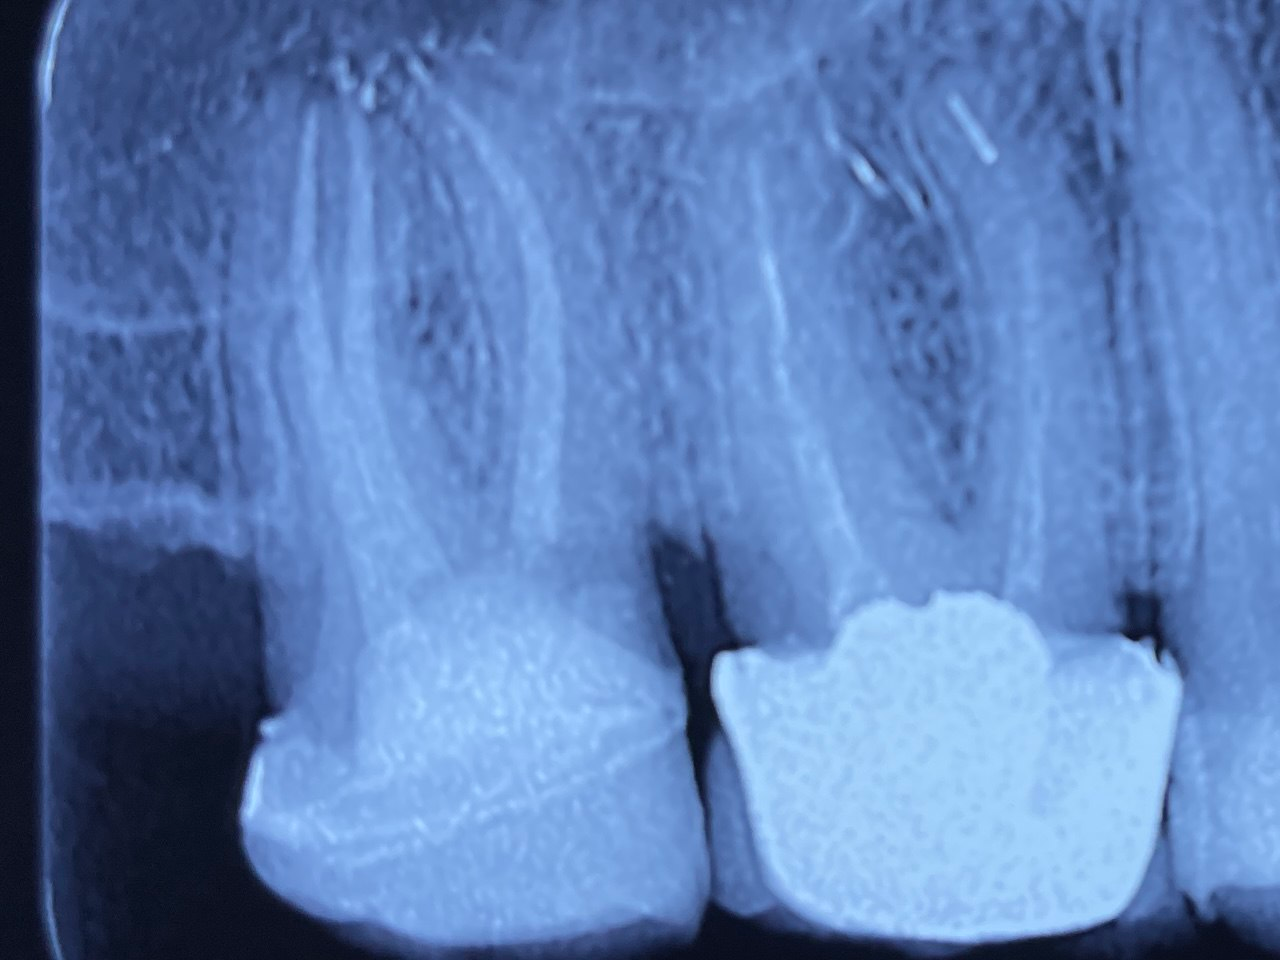

3. Evaluate the root canal treatment of tooth # 1.7?

4. Evaluate the root canal treatment of tooth # 3.6?